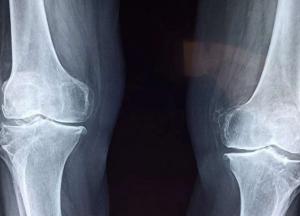

Названы ранние признаки остеопороза, которые нельзя игнорировать

Остеопороз поражает миллионы человек. Остеопороз часто считается «тихой болезнью». Человек может жить с этим заболеванием годами, прежде чем ему будет поставлен диагноз - но есть три ранних предупреждающих признака, на которые следует обратить внимание, передает FaceNews.ua.

Остеопороз возникает, когда образование новой кости не успевает за потерей старой кости, что приводит к потере плотности кости.

Кости людей с этим заболеванием со временем становятся слабее, что резко увеличивает риск переломов.

В самых серьезных случаях кости могут стать настолько хрупкими, что даже легкие нагрузки, такие как кашель или наклоны, могут вызвать болезненные переломы.